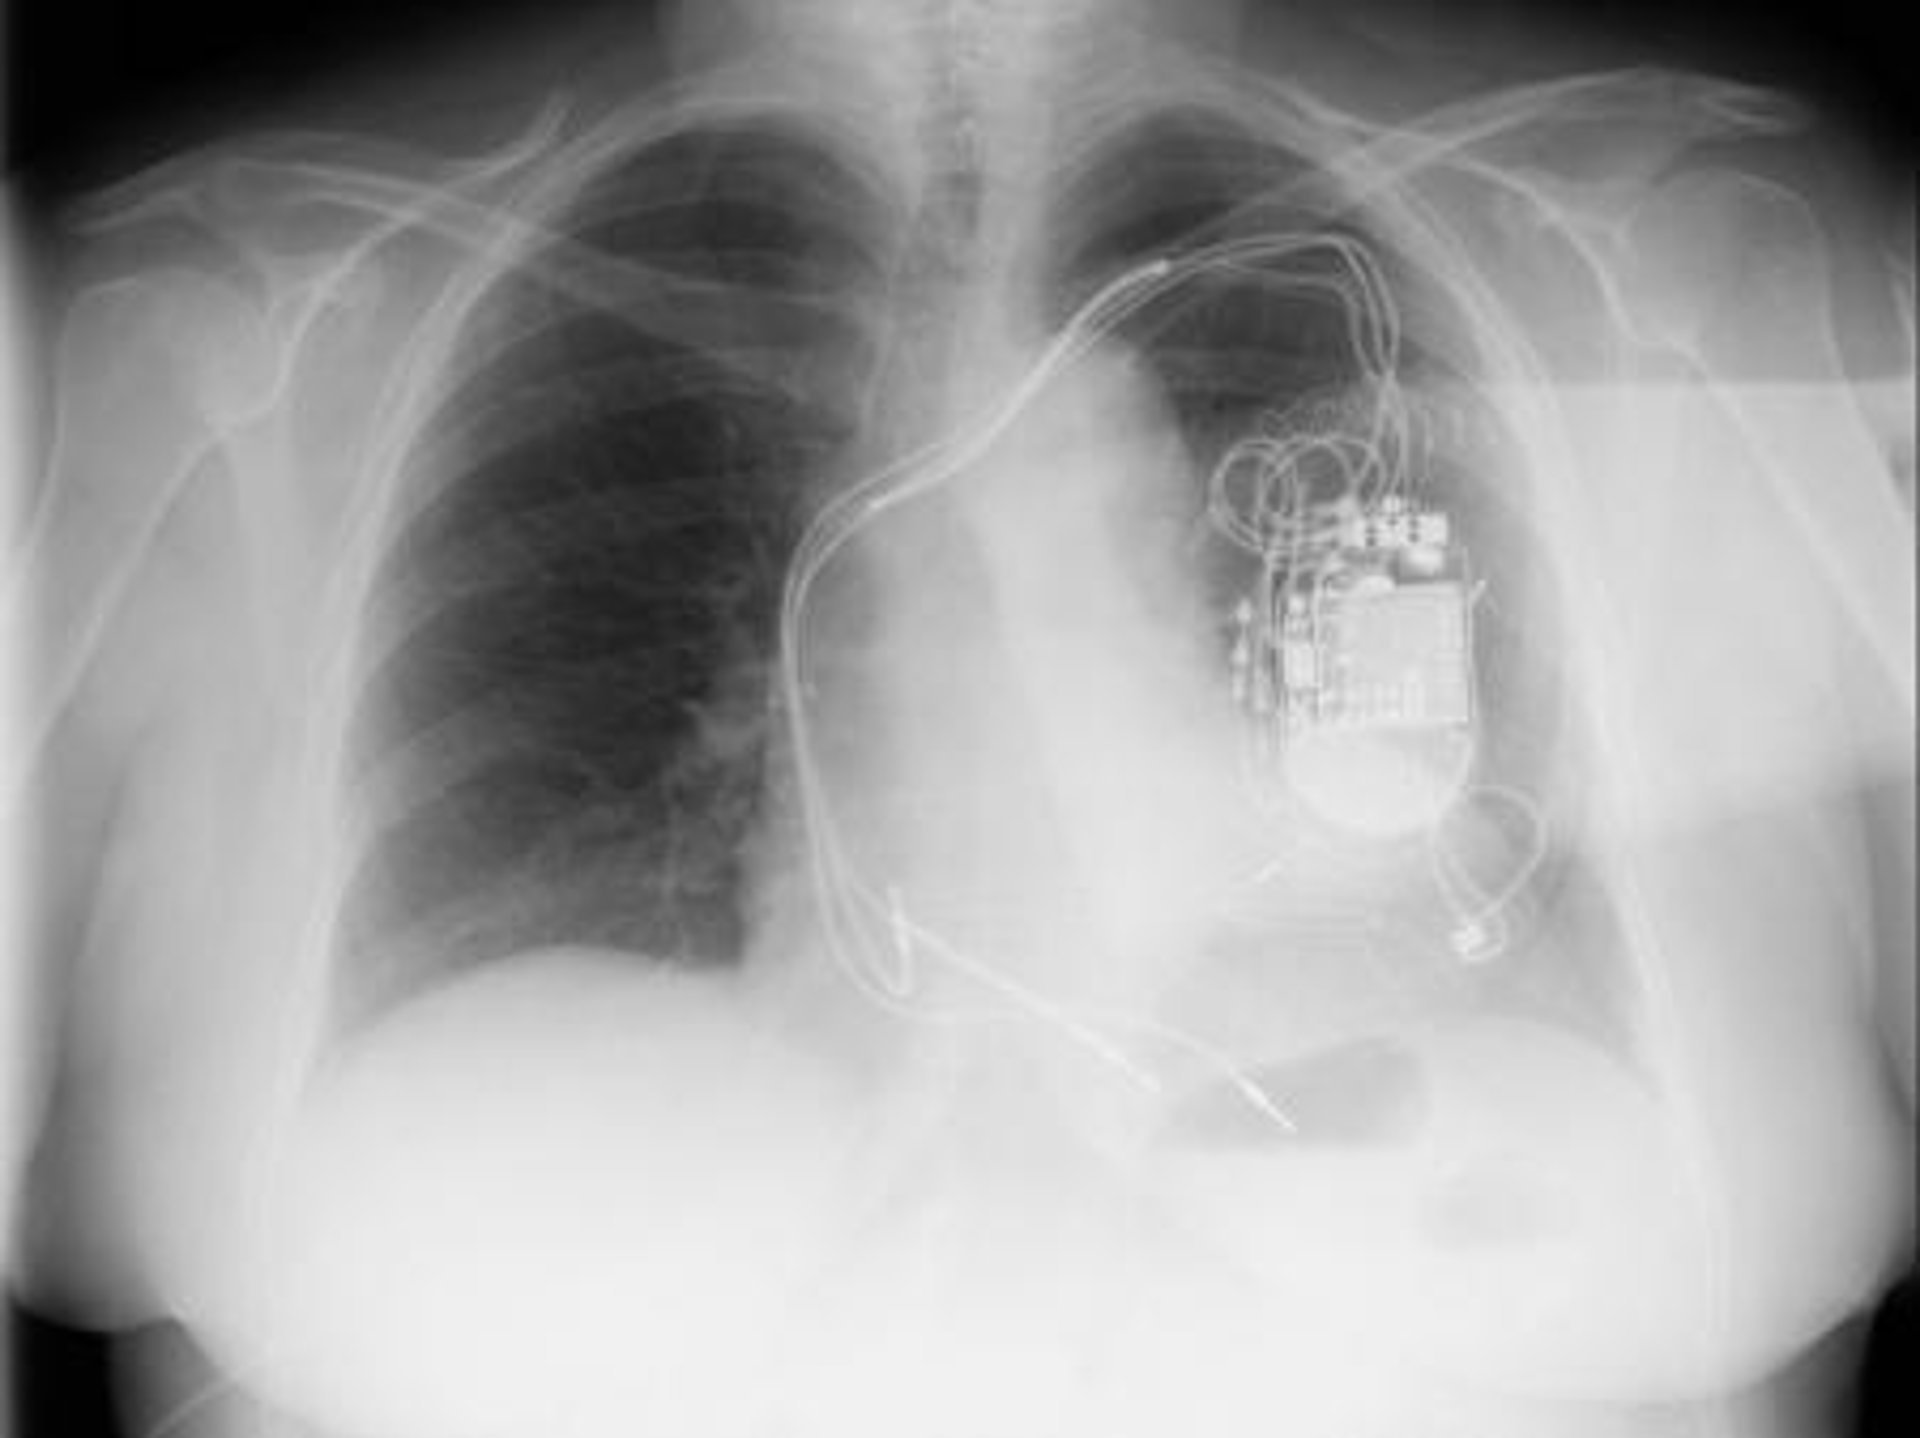

En el tratamiento de arritmias, Pascual confirma que se ha producido también un avance en los dispositivos empleados para evitar la muerte súbita. En concreto, confirma que en los casos de alto riesgo o que ya han sufrido episodios de este tipo, se les implanta un dispositivo llamado desfibrilador.

Hasta ahora, el doctor Pascual explica que estos dispositivos llevaban cables hasta el corazón para monitorizar la actividad cardiaca del paciente y les salvaba la vida en caso de arritmia mortal.

El avance fundamental en este caso --que comenzará a implantarse el año que viene-- es que los médicos comienzan a disponer de dispositivos más evolucionados que carecen de cables, y reciben el nombre de desfibriladores subcutáneos. Entre otras ventajas, su implante es más sencillo y evitan que los cables se infecten o se rompan, como puede ocurrir.